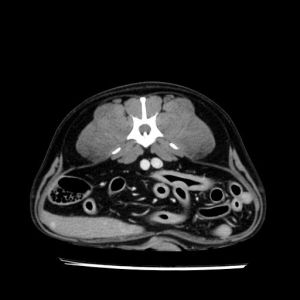

La lesione focale epatica , la ceus,la Tac e il chirurgo .